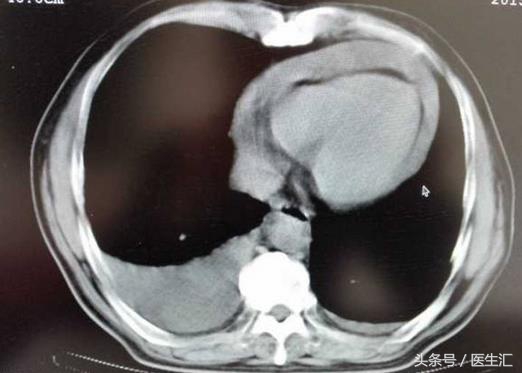

辅助检查:于本院心电图显示:窦性心律,各导联低电压,T波是低平和倒置。超声心动图显示:左房左室内径正常,射血分数74%,中到大量的心包积液。胸片显示:心界向两侧扩大,同时左侧有少量的胸腔积液。血常规正常,抗核抗体阴性,血沉23,风湿因子、抗链O是阴性的,免疫球蛋白和补体是阴性的。甲功显示:T3T4水平低,TSH的水平明显升高,升高约正常界值的15倍。

网络图片,非本病历插图